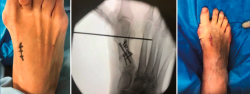

Figura 2. Detalles quirúrgicos de la osteotomía de apertura medial.

No se objetivó ningún caso de metatarsalgia de transferencia ni de pseudoartrosis. En las Figuras 2 y 3 se pueden ver detalles quirúrgicos de las osteotomías de apertura y cierre.